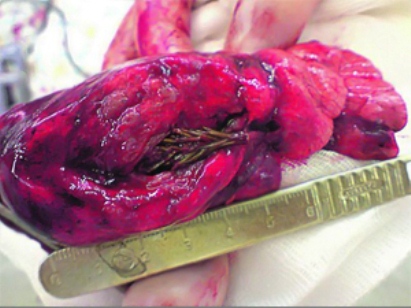

طول شاخه صنوبر حدود 5 سانتی متر بود. احتمالا دانه آن در اثر تنفس داخل ریه آرتیوم شده و بدن آرتیوم نتوانسته آن را دفع یا جذب کند و صنوبر با استفاده از محیط گرم و مرطوب ریه آرتیوم رشد کرده و به تدریج سبب بروز علائم درد و خلط خونی شده است.